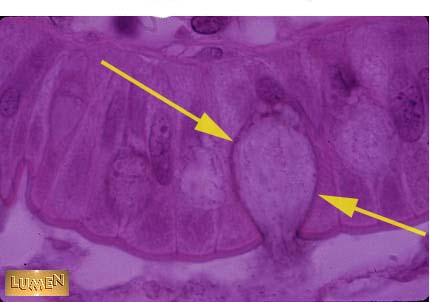

What type of cell is this?

Goblet cell